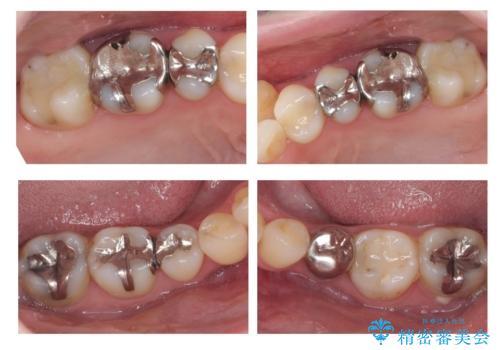

全体的な虫歯治療 銀歯をセラミックに

- 当院で矯正治療後、虫歯治療を一通り行いました。